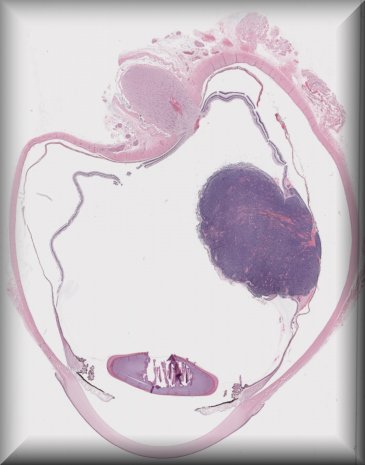

Patricia Chévez Barrios (Houston): 2 year-old-boy with history of group D unilateral retinoblastoma s/p systemic chemotherapy, cryotherapy and intravirteous chemotherapy. Enucleated for progressive disease. |

![]() |